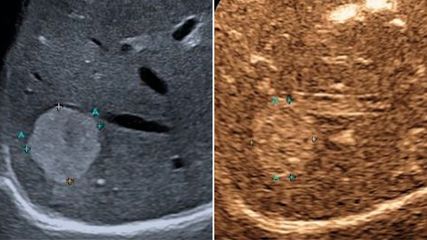

Prinzipielle Kontraindikationen für extrahepatische Eingriffe stellen eine schwere akute Hepatitis unabhängig von der Ätiologie, jedes akute Leberversagen und auch die alkoholische Steatohepatitis dar. In diesen Situationen sollte mit Ausnahme einer Lebertransplantation keine Operation angestrebt werden. Bei allen anderen Patient:innen sollten eine genaue Anamnese und klinische Untersuchung mit besonderem Augenmerk auf Zeichen der Dekompensation (Aszites, Enzephalopathie, vorausgegangene Varizenblutung) erfolgen. Ergänzend sollte eine Bildgebung mittels Sonografie oder CT durchgeführt werden, um Aszites und Splenomegalie als Zeichen der portalen Hypertension sowie das Vorliegen einer Pfortaderthrombose oder eines hepatozellulären Karzinoms zu beurteilen. Vor einer elektiven Operation sollte außerdem eine rezente endoskopische Abklärung auf das Vorliegen von Ösophagusvarizen erfolgt sein. Nach einer präoperativen Bandligatur sollte eine Wartezeit von 14 Tagen bis zur Operation eingehalten werden.

Sonografie der Leber – aktuelle Entwicklungen, quantitative Verfahren und klinische Bedeutung

Der vorliegende Übersichtsartikel fasst aktuelle technische Entwicklungen sowie klinische Anwendungen und Limitationen der Lebersonografie zusammen und diskutiert deren Stellenwert im ...